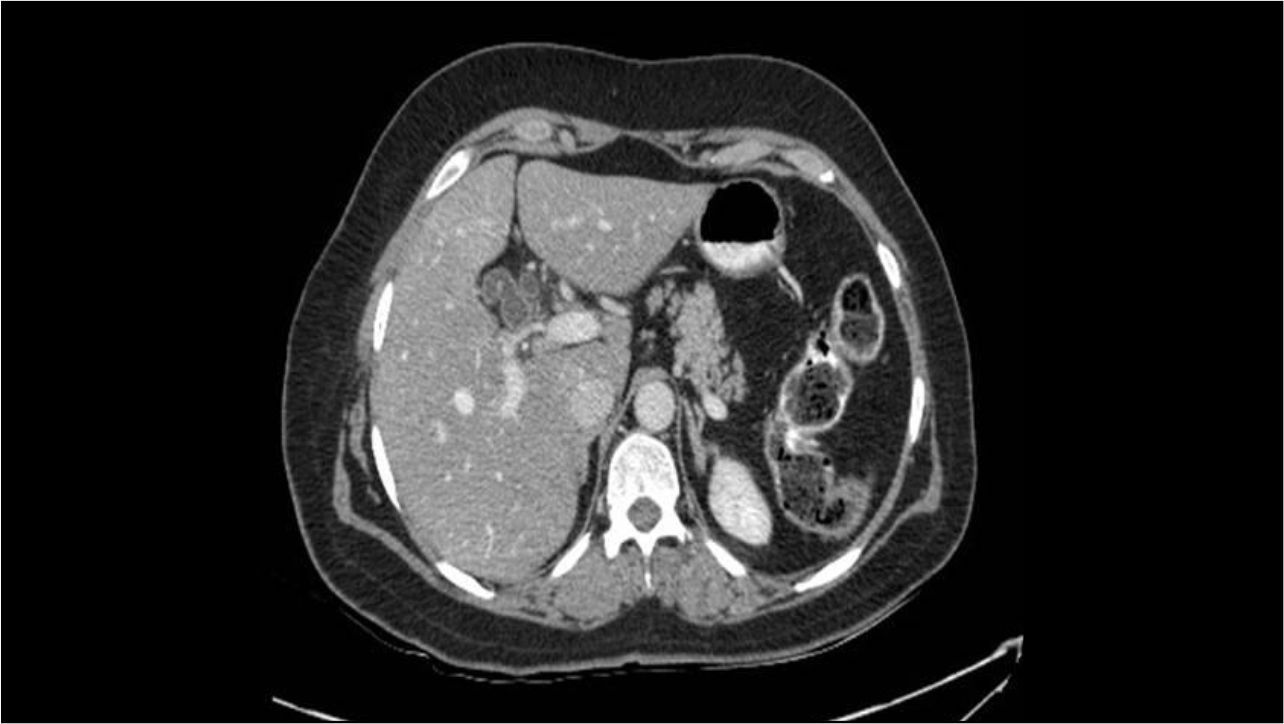

Primary hepatic neuroendocrine tumor (NET) or metastatic ileal NET – that is the question

carcinoid tumor-Primary hepatic neuroendocrine tumor (NET) or metastatic ileal NET – tha...

Surgery for intrahepatic cholangiocarcinoma (IHC)

intrahepatic cholangiocarcinoma-Surgery for intrahepatic cholangiocarcinoma (IHC) A mal...